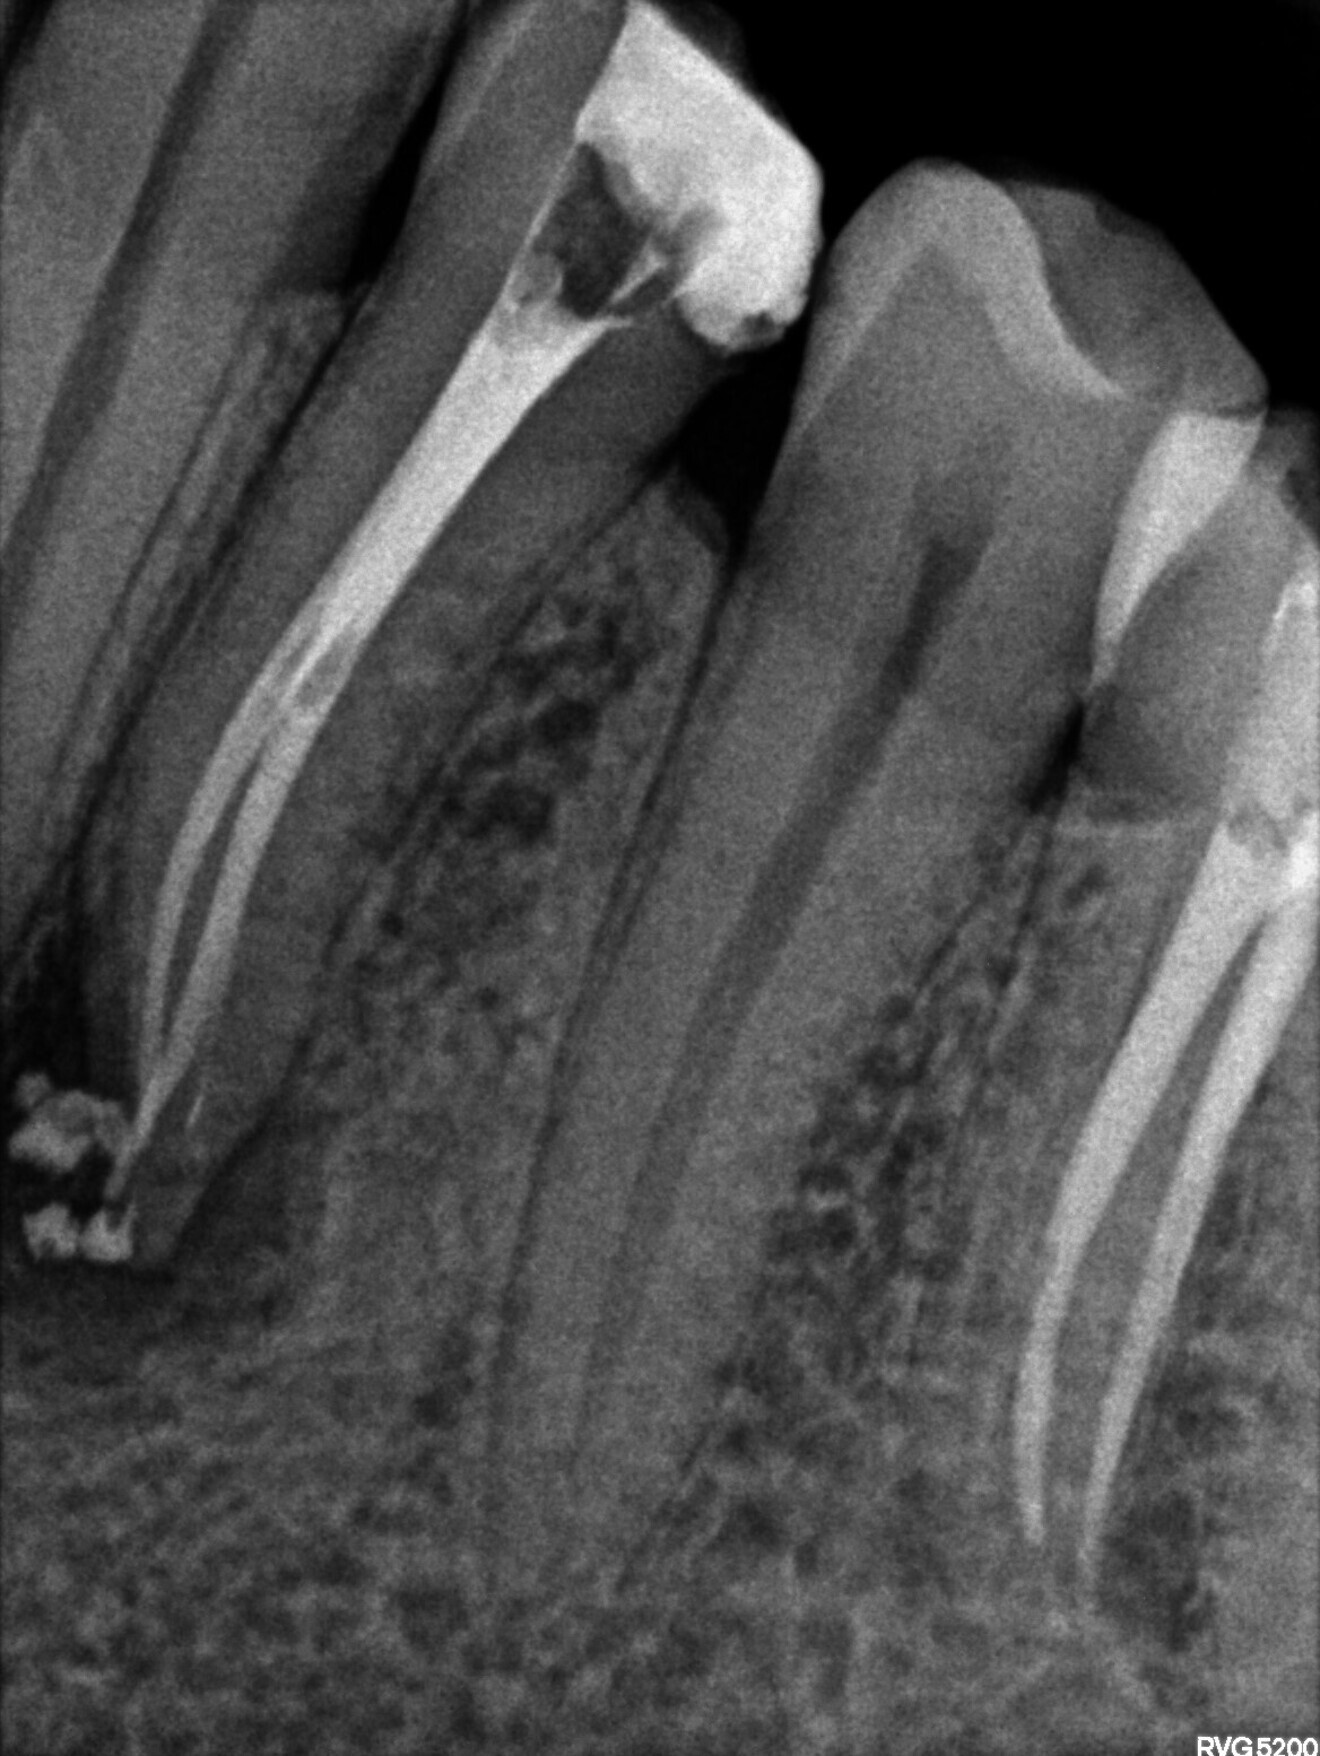

Fig 2: Pre-op radiograph

A patient presented with a large draining buccal abscess that showed a large peri apical lesion with an incompletely obturated canal on the pre-operative intraoral radiograph.